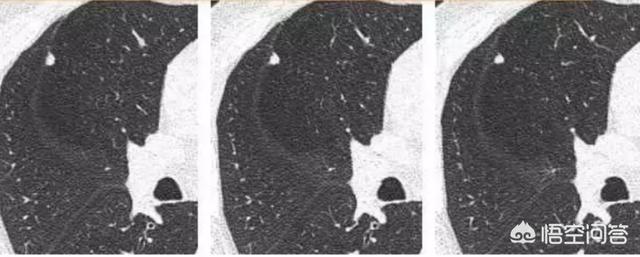

このような4ミリほどの小さな固形結節は滑らかで、悪性腫瘍の明らかな兆候は見られなかった。しかし、2年4ヵ月後:

後に病理検査で小細胞肺がんであることが確認された。